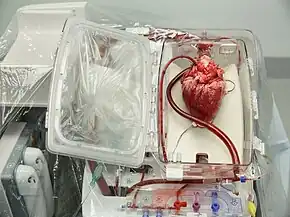

Donor retrieval

The donor is fully heparinised before the heart is retrieved and placed in cold saline in an insulated organ transport box.[1] Ischemic time is ideally limited to around 4 hours or less.[19]

Ex vivo machine perfusion is an emerging technology under investigation to create a similar environment around a beating donor heart while simultaneously keeping it warm.[48] It is being trialled in Australia,[49] the UK,[50] and others.[51]